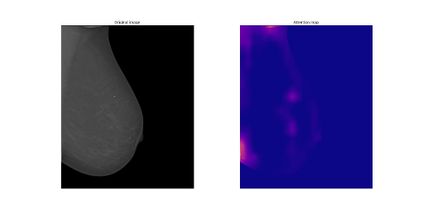

Breast cancer is the most widespread neoplasm among women and early detection of this disease is critical. Deep learning techniques have become of great interest to improve diagnostic performance. Nonetheless, discriminating between malignant and benign masses from whole mammograms remains challenging due to them being almost identical to an untrained eye and the region of interest (ROI) occupying a minuscule portion of the entire image. In this paper, we propose a framework, parameterized hypercomplex attention maps (PHAM), to overcome these problems. Specifically, we deploy an augmentation step based on computing attention maps. Then, the attention maps are used to condition the classification step by constructing a multi-dimensional input comprised of the original breast cancer image and the corresponding attention map. In this step, a parameterized hypercomplex neural network (PHNN) is employed to perform breast cancer classification. The framework offers two main advantages. First, attention maps provide critical information regarding the ROI and allow the neural model to concentrate on it. Second, the hypercomplex architecture has the ability to model local relations between input dimensions thanks to hypercomplex algebra rules, thus properly exploiting the information provided by the attention map. We demonstrate the efficacy of the proposed framework on both mammography images as well as histopathological ones, surpassing attention-based state-of-the-art networks and the real-valued counterpart of our method. The code of our work is available at https://github.com/elelo22/AttentionBCS.